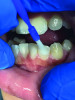

(6.) Fluoride varnish is one of the most common dental products used to help protect vulnerable tooth surfaces.

Figure 6

(7.) Fluoride varnish is one of the most common dental products used to help protect vulnerable tooth surfaces.

Figure 7

A thin fluoride-rich layer of enamel is compromised during debridement and polishing procedures. This layer can take upwards of 3 months to regenerate, leaving the tooth susceptible to daily sugar and acid attacks, which can result in a number of dental conditions such as caries and dentinal hypersensitivity. It is prudent for the clinician to treat and protect the compromised surfaces. As a preferred quick and easy in-office treatment, fluoride varnish is one of the most common dental products on the market to help protect vulnerable tooth surfaces until patients return for their next recare visit. Most varnish materials are comprised of a concentrated form of sodium fluoride (NaF) suspended in an alcohol- and resin-based solution with some additional additives, including a film-forming agent, flavors, sweetener such as xylitol (which has therapeutic benefits as well), and additives that aid in remineralization20,21 (Figure 5 through Figure 7). Examples include products such as Colgate® PreviDent® Varnish (Colgate Oral Health), FluoroDose® (Centrix), and ACCLEAN® 5% Sodium Fluoride Varnish (Henry Schein).

Once varnish is applied to the tooth surface, fluoride ions are attracted to the demineralized areas and integrate with hydroxyapatite to begin reforming the fluoride-rich enamel layer on the tooth surface.21 Most varnish products have a solubility profile that permits sustained release of fluoride over a specified period of time, offering teeth even greater protection over a longer duration.